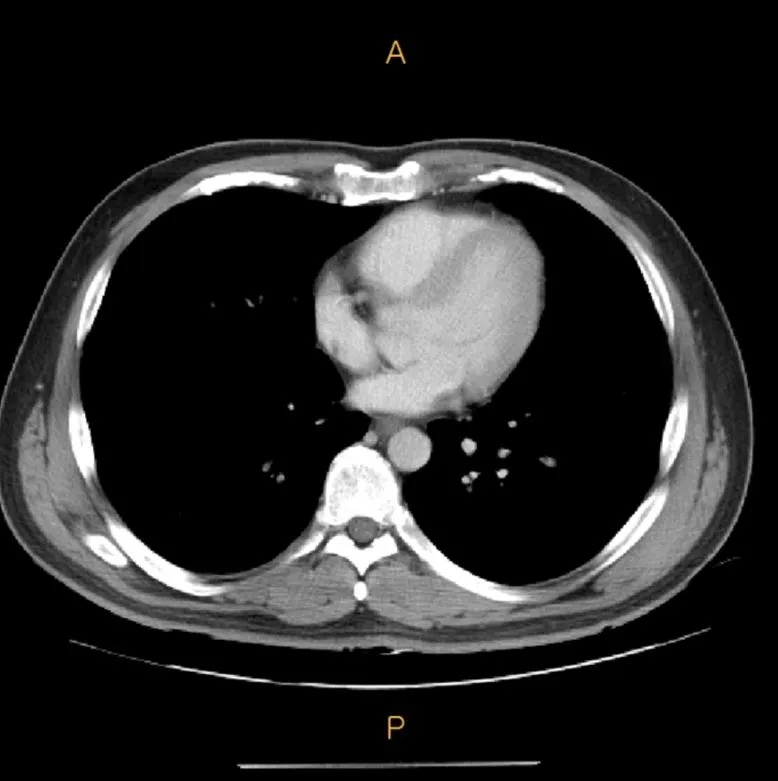

위의 사진이 바로 CT입니다. 이 동그란 도넛 안에는 빙글빙글 돌아가는 X-ray 촬영 장치가 있습니다. X-ray가 돌아가면서 촬영을 하면 그것을 컴퓨터가 재합성해서 아래와 같이 단층 사진을 만듭니다. (이 역시 제 사진입니다.)

CT.JPG